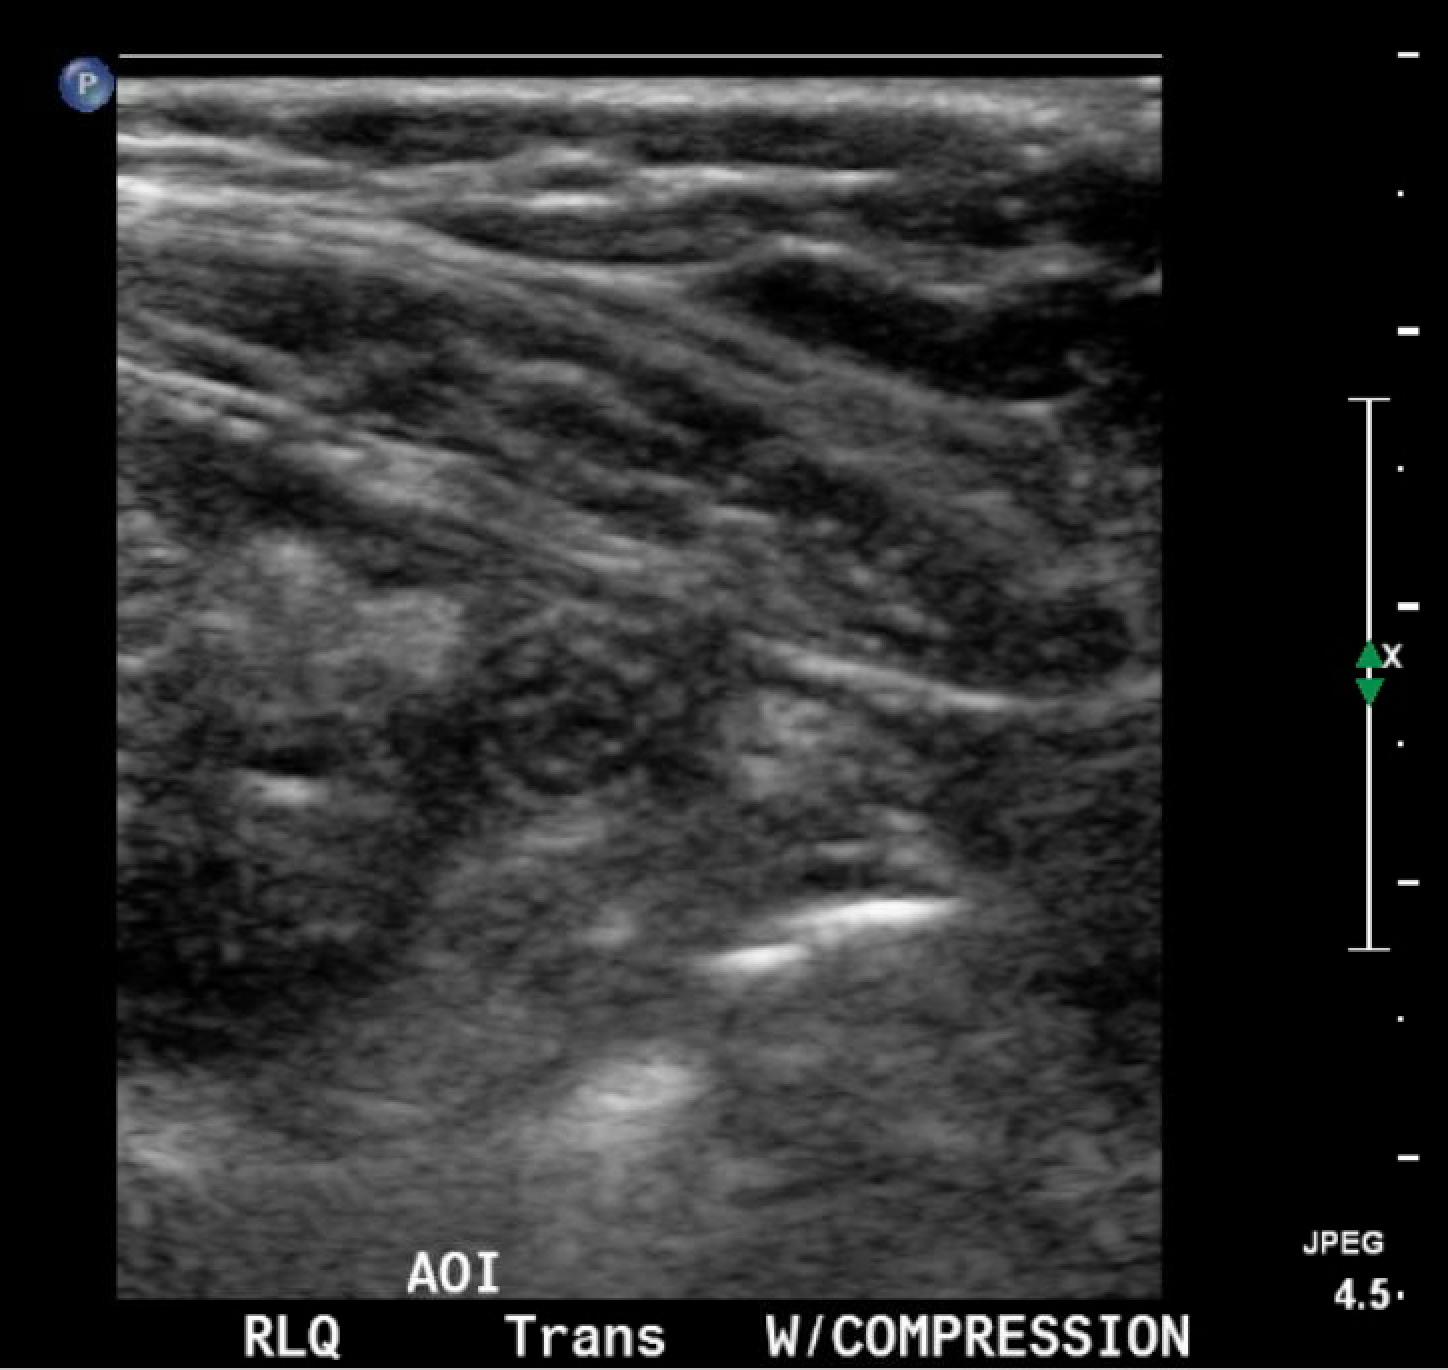

In the long axis video, the appendix appears as an enlarged, non-compressible, blind-ending tubular structure (white arrow) with distinct appendiceal wall layers and lack of peristalsis. In the short axis video, the appendix appears as a target sign (yellow arrow) between the abdominal and psoas muscles. The maximal outer diameter (MOD) measures 11.8mm and the appendix wall measures 0.17mm. There is trace adjacent free fluid and echogenic periappendiceal fat. Transverse axis video and image (red arrow) demonstrate that the appendix is not compressible. These findings are consistent with acute appendicitis.